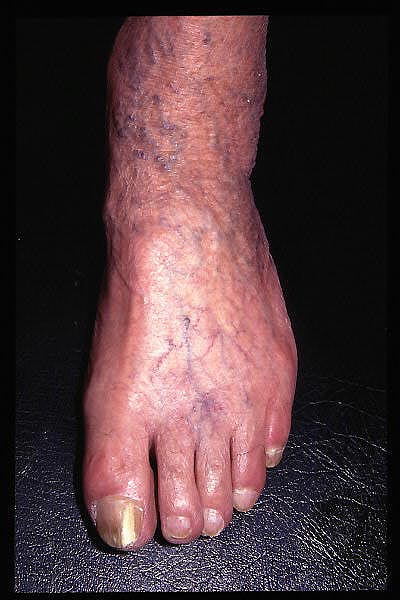

Insuficiencia venosa crónica